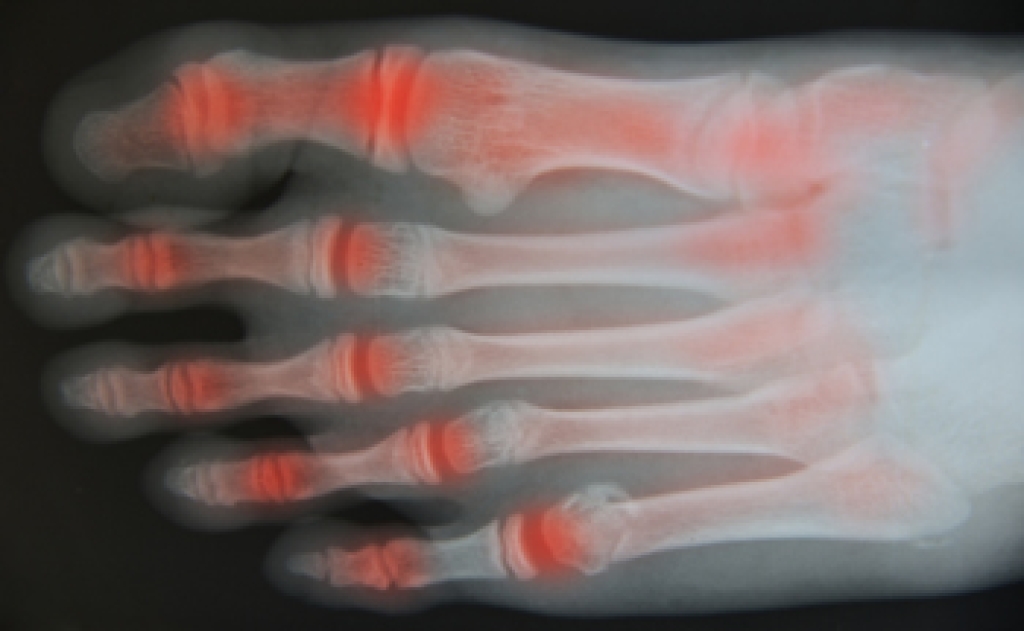

Elbow pain can make even simple tasks challenging, often resulting from repetitive movements, strain, or injuries. Conditions like tennis elbow, golfer’s elbow, and nerve entrapment are common culprits, leading to inflammation and discomfort in the tendons or surrounding tissues. Whether caused by sports, work activities, or an accident, persistent elbow pain can hinder mobility and strength.

Symptoms may range from sharp pain and stiffness to numbness or a weakened grip, interfering with daily life. While pain relief methods like rest can help, they may not address the underlying problem.

Chiropractic care focuses on identifying and treating the source of elbow pain. Through gentle adjustments, soft tissue therapies, and targeted exercises, chiropractors relieve tension, improve joint function, and reduce inflammation. This holistic approach helps not only to ease pain but also to prevent future issues, ensuring long-term comfort and mobility.